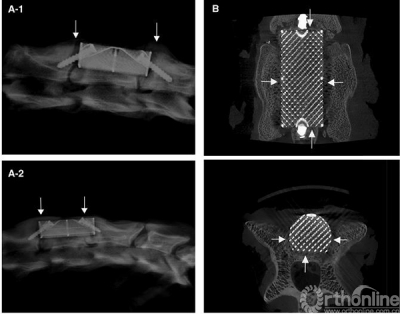

Figure 1.A-1 , SEM image of the implant surface and method of measuring pore size.A-2, Implant strain—stress curve, the arrow indicates trabecular structure fractures under corresponding compressive strength.B shows the implant product. SEM indicates scanning electron microscope.

The compressive strength and Young’s modulus were 26.8 MPa and 12.9 GPa respectively. The mean compressive strength and Young’s modulus of the 10 samples were 27.61 ± 1.21 MPa and 14.24 ± 1.11 GPa, respectively. Fig 1b shows the product of SSAVB.

Fig 2a depicts the x-ray films from group A and B.Table 2 depicts the height of the fusion segments after surgery and before sacrifice, there was no significant difference in each group (p = 0.07 and 0.14 respectively).

Lateral radiographic film before sacrifice of group A (Figure 2a-1) and group B (Figure 2a-2). Gaps exist between the SSAVB and C4 posterior vertebral wall as well as C3 and C5 vertebral body which became fuzzy at the 6th week and almost disappeared at the 12th week, arrows indicate the growth of bone bridge. From the Micro—CT image of the implant (Figure 1b) we can observe the bone ingrowth.

We observed the bone ingrowth directly through Micro—CT. Fig 2b shows that the bone ingrowth from posterior vertebral wall and both sides of the vertebral body can be observed.